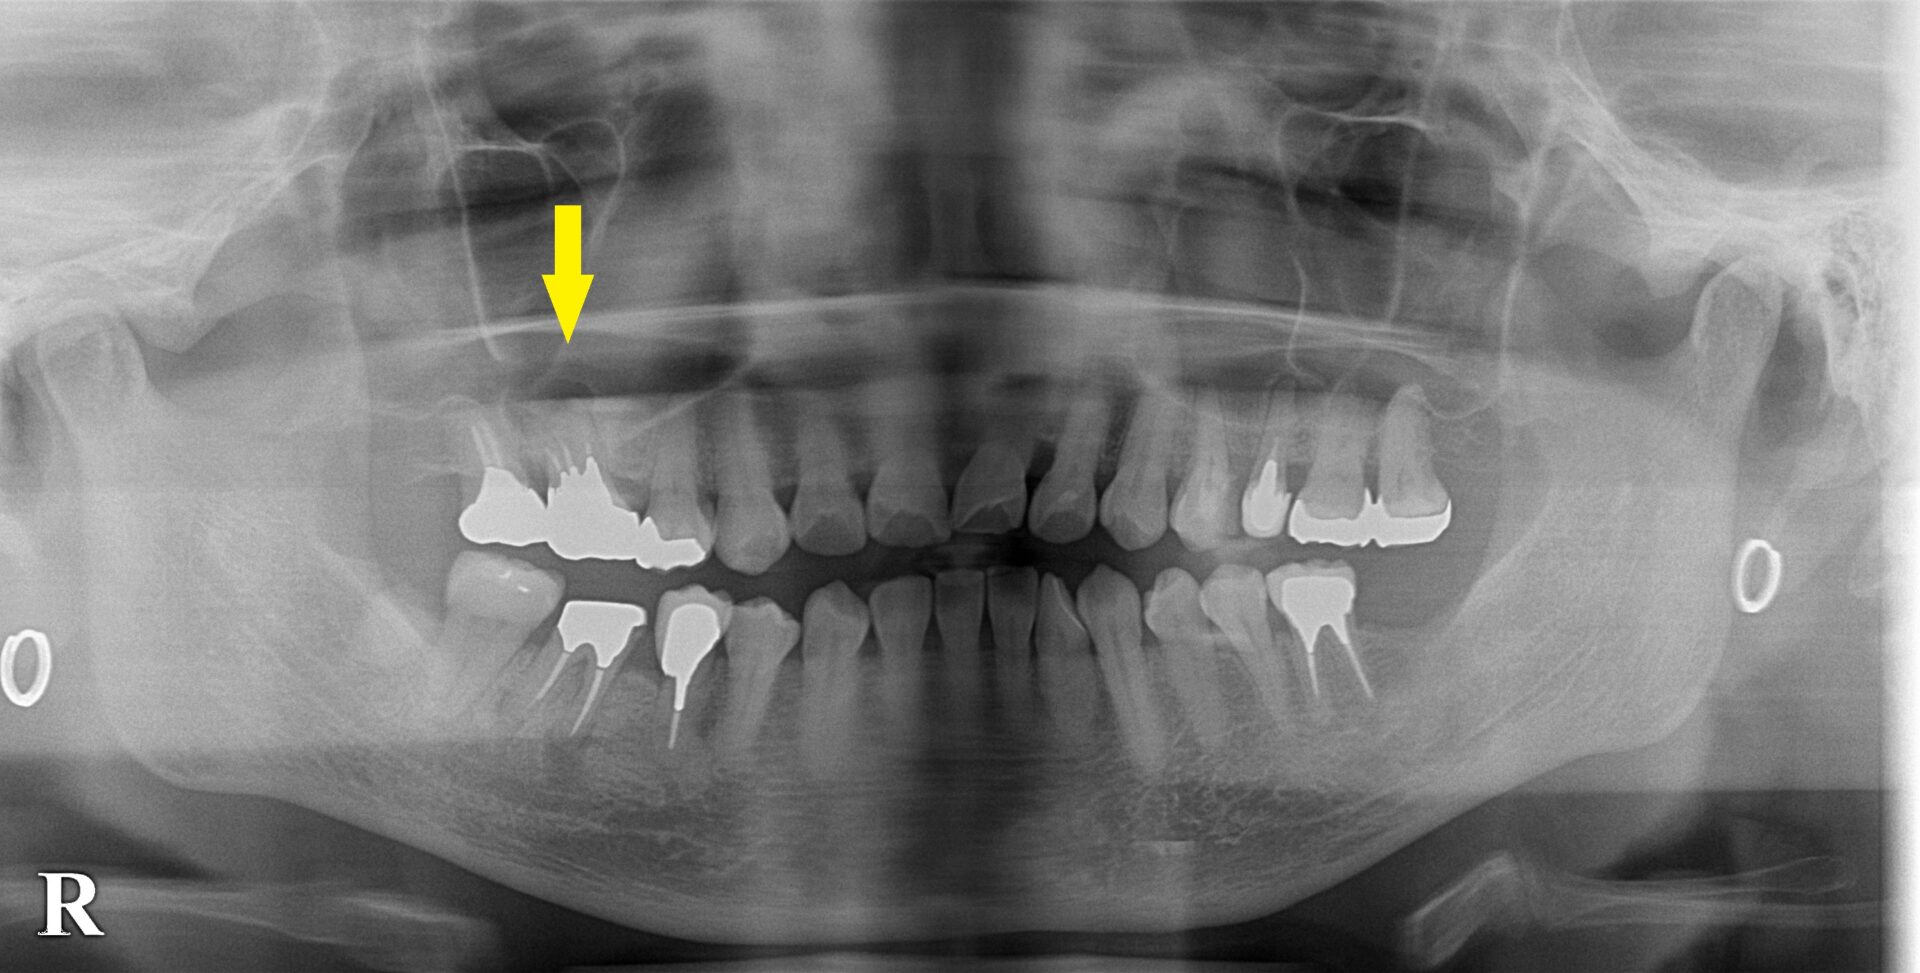

右上顎大臼歯、ワイドショートインプラント

右上顎の第一大臼歯が腫れて、膿が出て、幾度か根管治療をされたのですが、症状は改善せず、再発を繰り返していたそうです。

もう抜歯しなければ、症状は消失しないと言われたため、抜歯してインプラントにしたいとのご希望で、来院されました。

まずは抜歯して、数か月治癒を待ちました。

CTを撮影してみると、骨の高さが3mm程しかありませんでした。

下の写真、2段目が手術前、3段目が手術後のCTです。